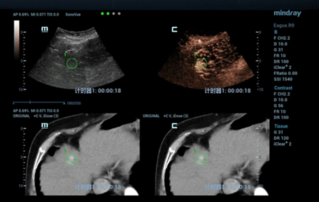

![microwave-ablation-for-recurrent-liver-cancer-assisted-by-fusion.thumb.319.319 Pismo dotycz?ce USG 1 ÔÇô Ablacja z u?yciem mikrofal w przypadku nawrotowego raka w?troby, z obrazowaniem fuzyjnym]() Pismo dotycz?ce USG 1 ÔÇô Ablacja z u?yciem mikrofal w przypadku nawrotowego raka w?troby, z obrazowaniem fuzyjnymPismo dotycz?ce USG | Systemy obrazowania medycznego 2021-12-21

Pismo dotycz?ce USG 1 ÔÇô Ablacja z u?yciem mikrofal w przypadku nawrotowego raka w?troby, z obrazowaniem fuzyjnymPismo dotycz?ce USG | Systemy obrazowania medycznego 2021-12-21 -